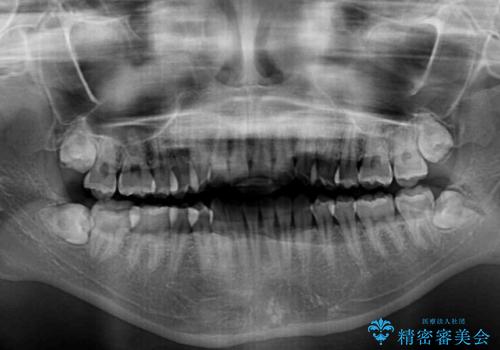

- 前に出ている上顎前歯が気になるとのことで来院された患者様です。

インビザラインを用い、IPR(歯と歯の間を削る)と歯列全体を後方に移動させることで、可能な限り前歯の突出感を改善することとしました。

元々の歯列も整っており、横顔の印象の出っ歯ではなかったため、仕上がりに満足できない可能性があると心配しておりましたが、口が閉じやすくなり、患者様には大変満足していただきました。